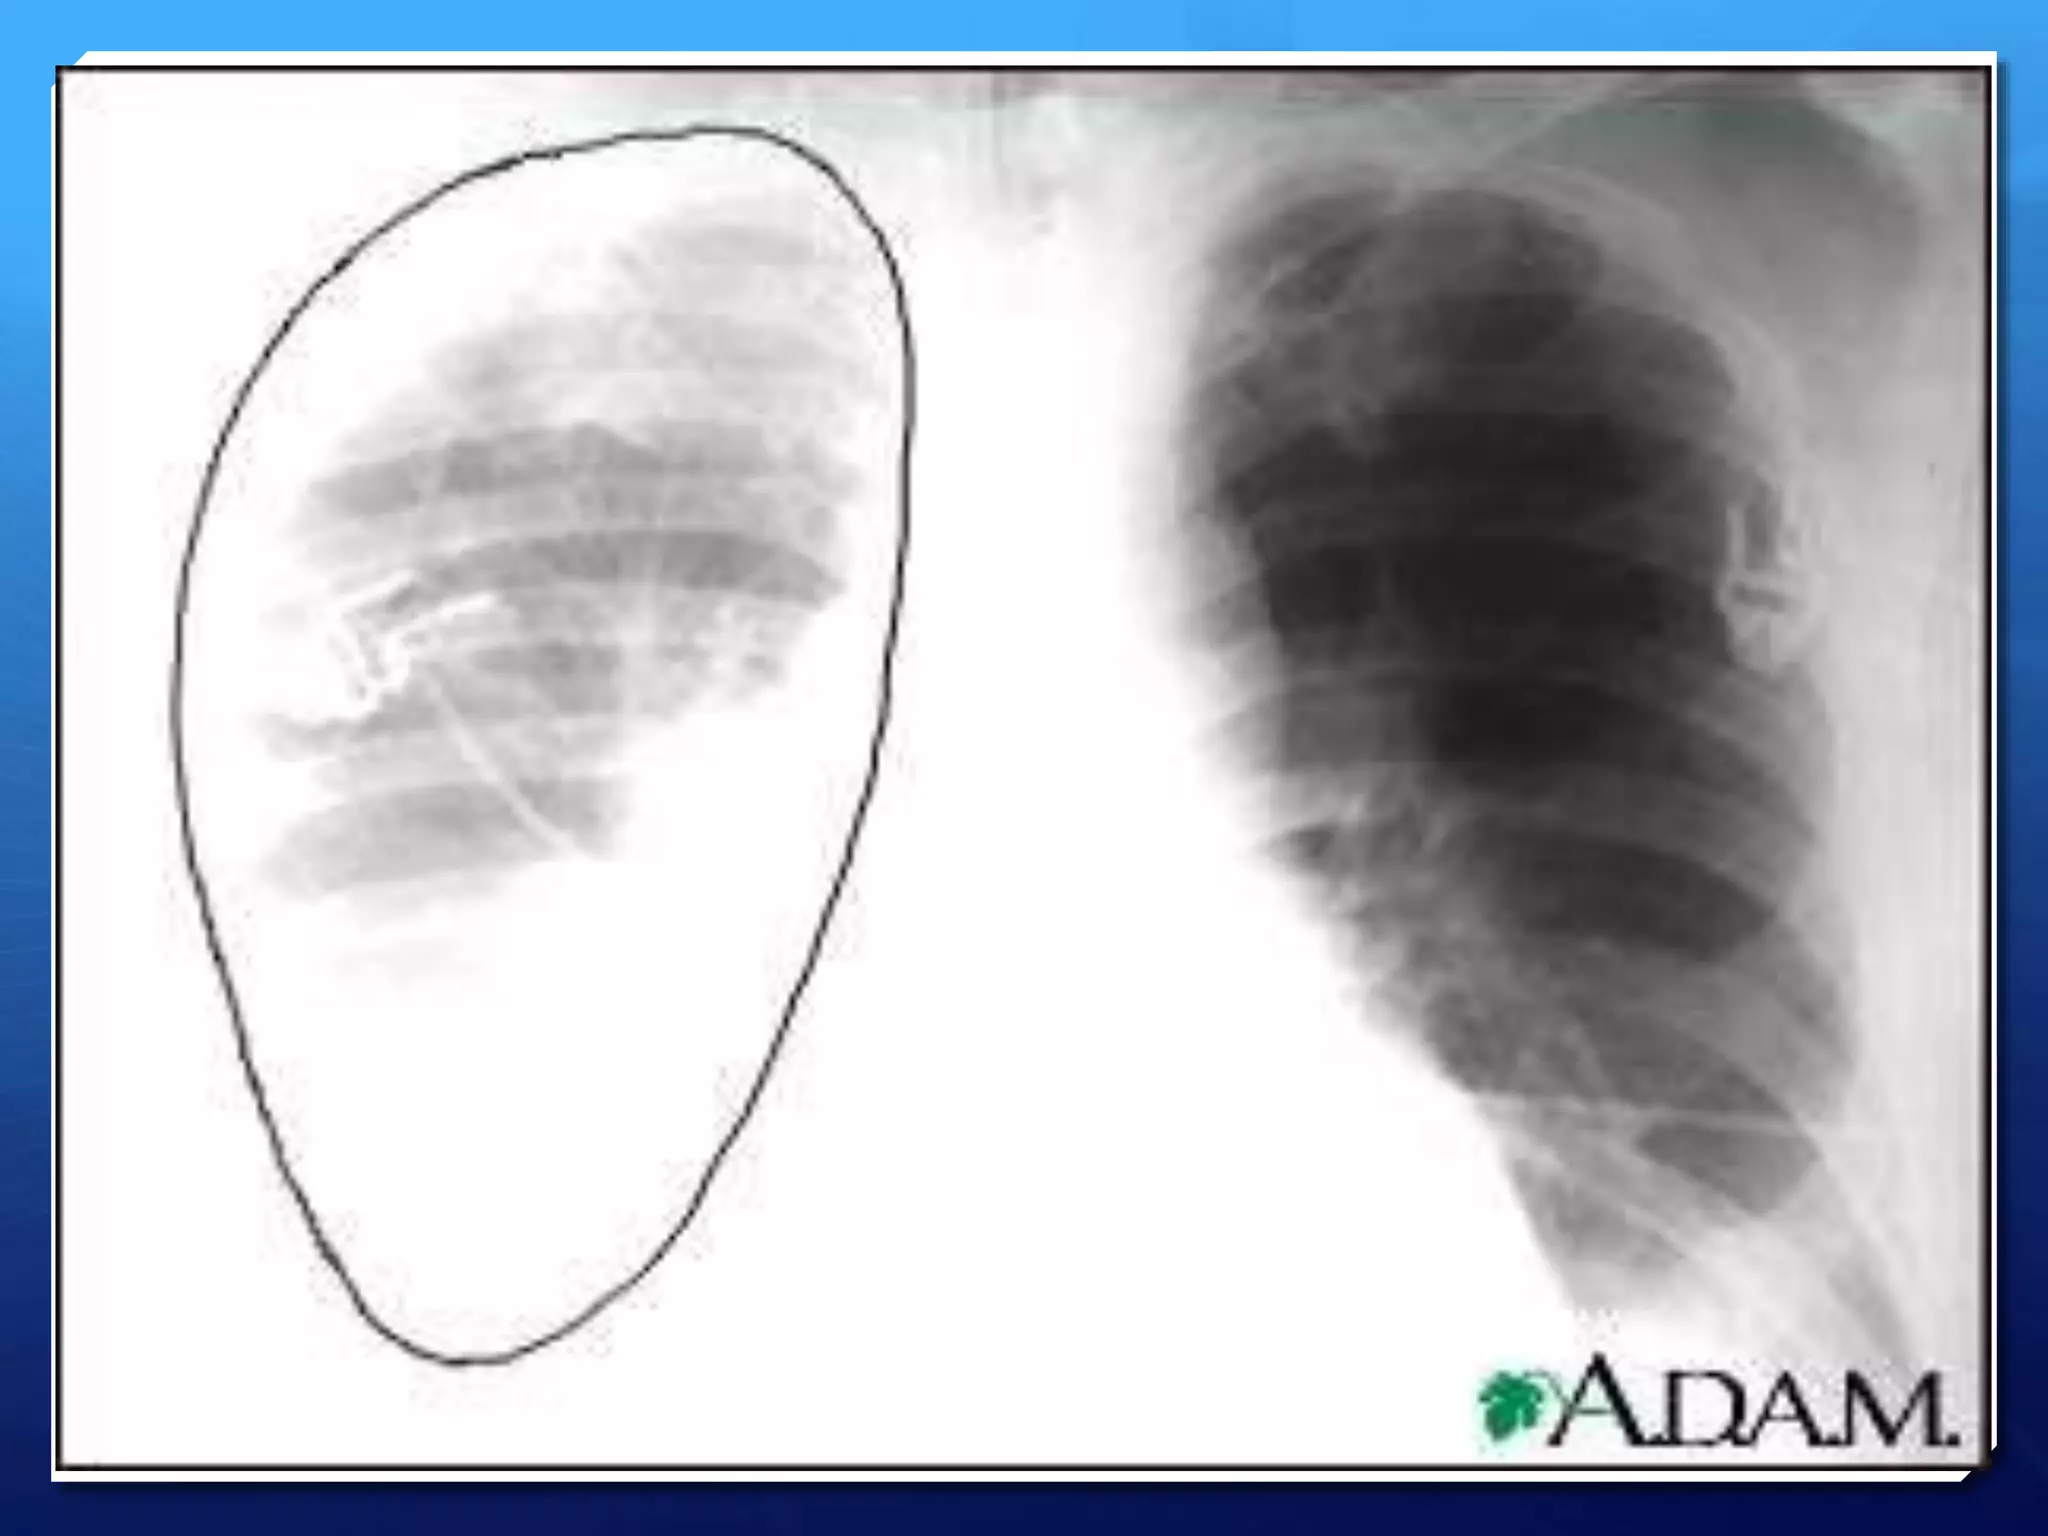

Upright chest x-ray

 White visceral pleural line

 Absence of vessel markings peripheral to line

Upright chest x-ray White visceral pleural line  Absence of vessel markings peripheral to line